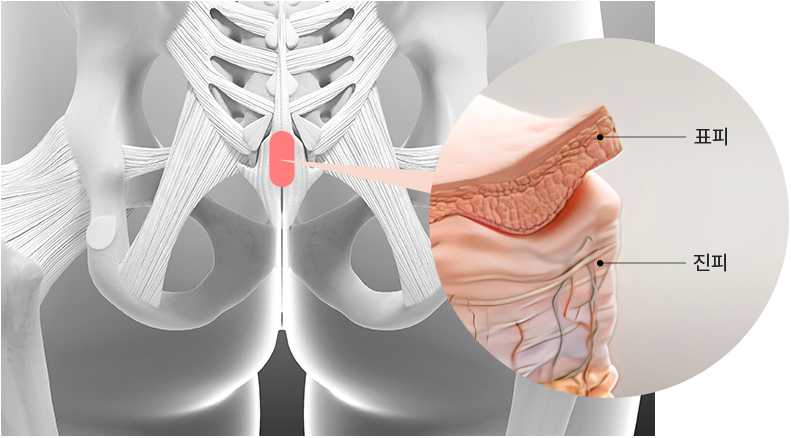

본인의 신체(주로 엉덩이 사이 꼬리뼈 부위)에서 진피 조직을 채취하여

코끝이나 콧대에 이식하는 수술 방법입니다.

step 01. 자가진피 채취 및 봉합

엉덩이 골 사이의 안쪽을 절개하여 가장 적합한

진피를 채취하고 시간이 지나면 흉터가 눈에 띄지 않게

숨겨집니다.